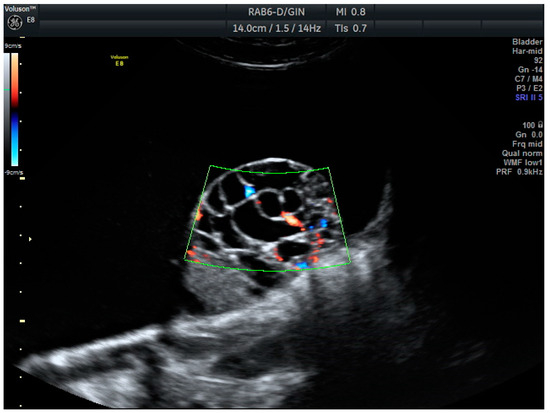

Years later, in 2008, the IOTA Simple Rules (SR) were among the first systems to provide a standardized framework for classifying adnexal masses based on ten rules. The benignity features (B) included unilocular cysts (B1) solid components < 7 mm (B2), acoustic shadows (B3), regular multilocular tumor < 100 mm (B4), and negative color maps (B5). The malignancy features (M) contained irregular solid tumors (M1), ascites (M2), ≥4 papillae (M3), multilocular irregular solid tumors > 100 mm (M4), and high vascularization (M5) (Figure 1 and Figure 2). According to SR, masses are classified as malignant if one or more malignancy features are present and no benignity features are observed; benign if one or more benignity features are present and no malignancy features are observed; and inconclusive if both types of features or none are present [5]. These rules have been extensively validated in the literature and have been shown to have good diagnostic performance [6,7]. In 2016, the IOTA Simple Rules Assessment was developed, integrating the Simple Rules with the consideration of whether the patient was treated at an oncology center, improving diagnostic accuracy [8], and adding a percentage of the probability of malignancy.

Figure 2. Serous caricinoma. Multicystic mass with a solid papilla inside with a high score Doppler color (score color 4).